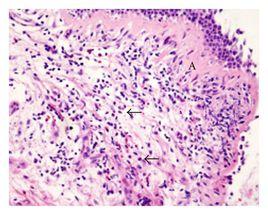

1、誘導痰嗜酸性粒細胞計數:明顯增多,>3%為有意義。

2、ECP檢測:採用螢光酶免疫法測定誘導痰或BALF中ECP量,嗜酸粒細胞性支氣管炎患者明顯增多。